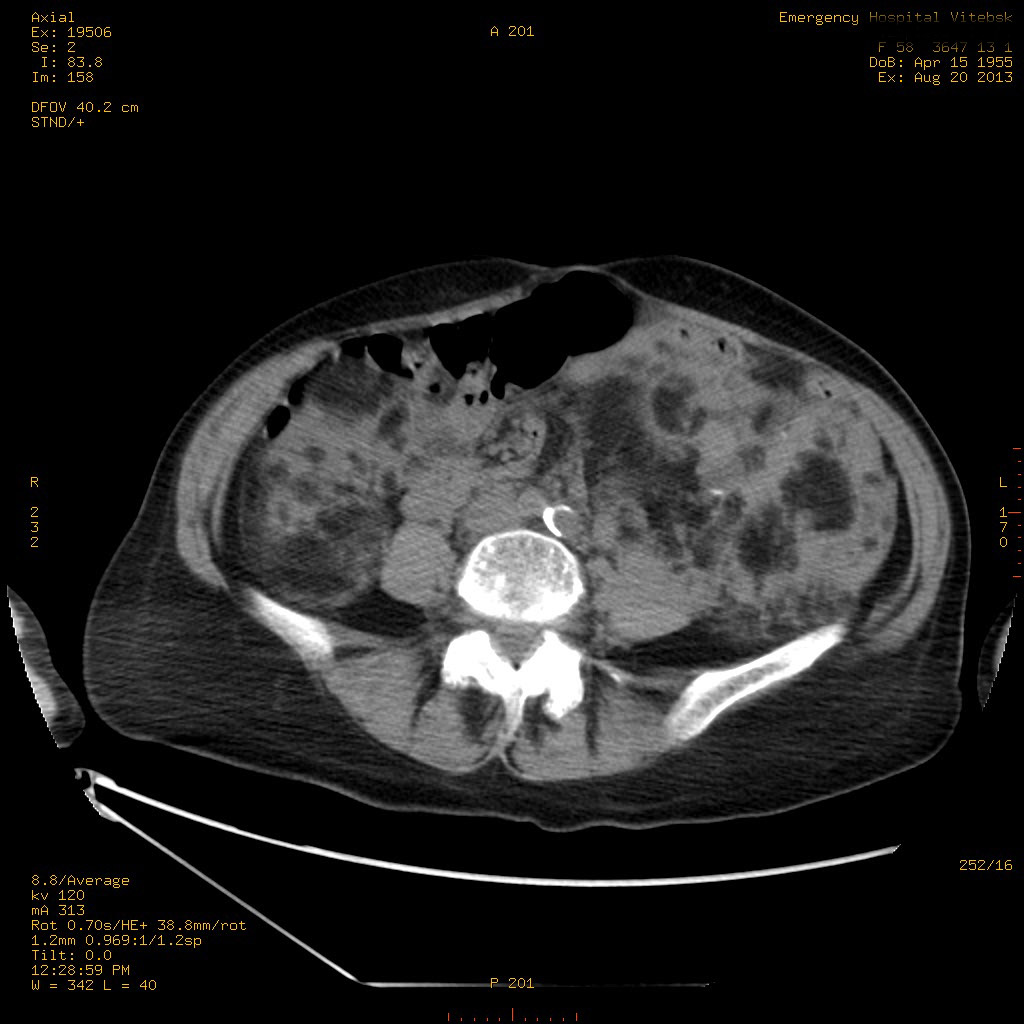

УЗИ почек - туберозный склероз

Пожилая женщина с нормальными мочевиной и креатинином.

Ангиомиолипоматоз почек , думаю компонент туберозного склероза.

Да, туберозный склероз.

Случай консультирован на кафедре радиологии Католического университета г.Лёвен (Бельгия) - зав каф. профессор Р.Оуен.